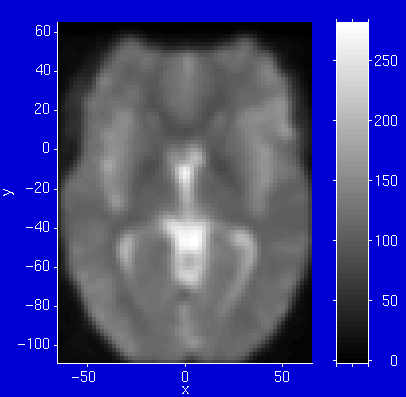

Slices

• abhängig von Position des Cursors

• Werte / Schnittebene fix